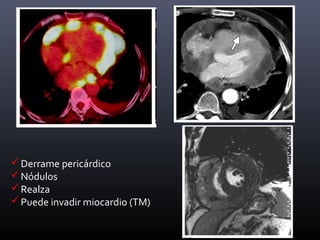

Derrame pericárdico

Nódulos

Realza

Puede invadir miocardio (TM)